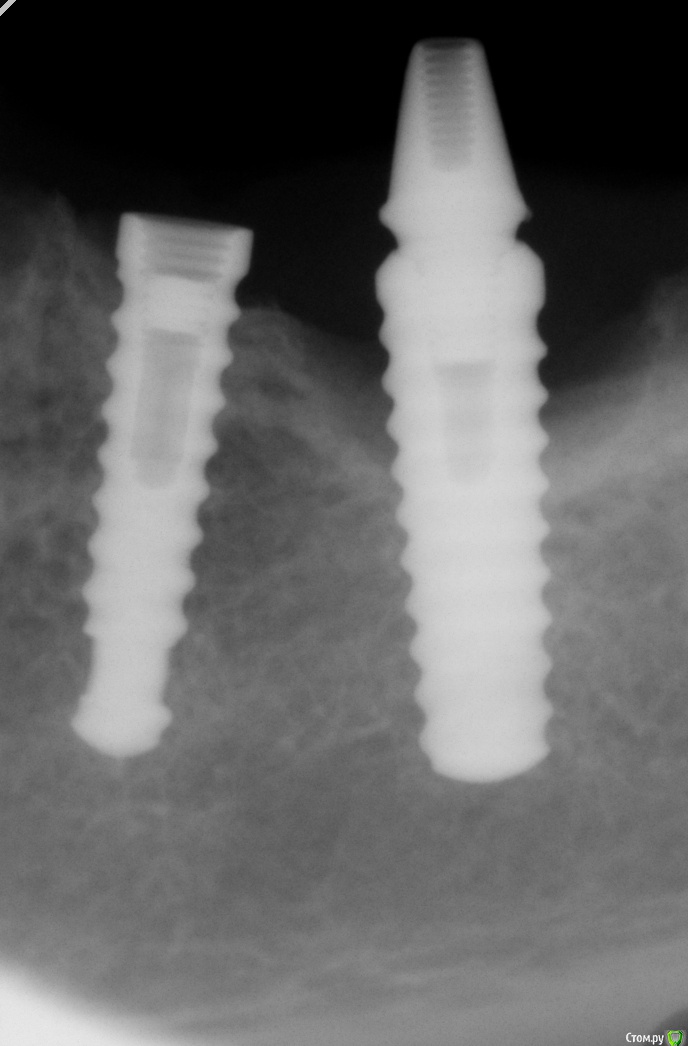

Uliana A. Опубликовано 17 сентября, 2015 Поделиться Опубликовано 17 сентября, 2015 Уважаемые коллеги,помогите пожалуйста определиться,что это за система имплантатов? Ссылка на комментарий

k.t.m. Опубликовано 17 сентября, 2015 Поделиться Опубликовано 17 сентября, 2015 Вроде как там винт сломан? Ссылка на комментарий

gum Опубликовано 17 сентября, 2015 Поделиться Опубликовано 17 сентября, 2015 Да это радикс и винт сломан. Винт дрстать, а вот соседний имплантат наверное убирать, хотя при отсутствии воспаления и адекватной нагрузке может и послужить еще )) наблюдал похожие работы на радиксе Ссылка на комментарий

Uliana A. Опубликовано 17 сентября, 2015 Автор Поделиться Опубликовано 17 сентября, 2015 Да,винт действительно сломан, думаю как бы его аккуратнее достать. ПО поводу дистального имплантацию веду переговоры с хирургом. Ссылка на комментарий

Bioalex Опубликовано 23 сентября, 2015 Поделиться Опубликовано 23 сентября, 2015 Это имплантат Radix. Серия IIS. Ссылка на комментарий

Uliana A. Опубликовано 5 октября, 2015 Автор Поделиться Опубликовано 5 октября, 2015 Продолжение будет?Было принято решение, не протезировать данный участок,на этих имплантатах. Из-за высокого риска утраты дистального имплантатах. Пациентке предложено удаление имплантатов, и последующее лечение,после восстановления объема кости Ссылка на комментарий

RuStom Опубликовано 5 октября, 2015 Поделиться Опубликовано 5 октября, 2015 А кто подскажет, почему у этого имплантата такой дефект костной ткани?Почему только у одного?Перегрузка? За какое время может произойти такая убыль? Это годы или месяцы? Ссылка на комментарий

Uliana A. Опубликовано 7 октября, 2015 Автор Поделиться Опубликовано 7 октября, 2015 А кто подскажет, почему у этого имплантата такой дефект костной ткани?Почему только у одного?Перегрузка?За какое время может произойти такая убыль? Это годы или месяцы? Конкретно в этой ситуации, я думаю сложились несколько факторов из-за которых произошла резорбция : 1-пациентка уже год назад потеряла коронки и сейчас ходит по клиникам и ищет помощи,т.к. в клинике где устанавливались импланты в помощи ей отказали. Она жует этим аббатментом, на дистальном имплантате, травмирует десну, забивается пища в пространство между имплантом и десной и вот результат.2- первоначально скорее всего была перегрузка этой области. Ссылка на комментарий